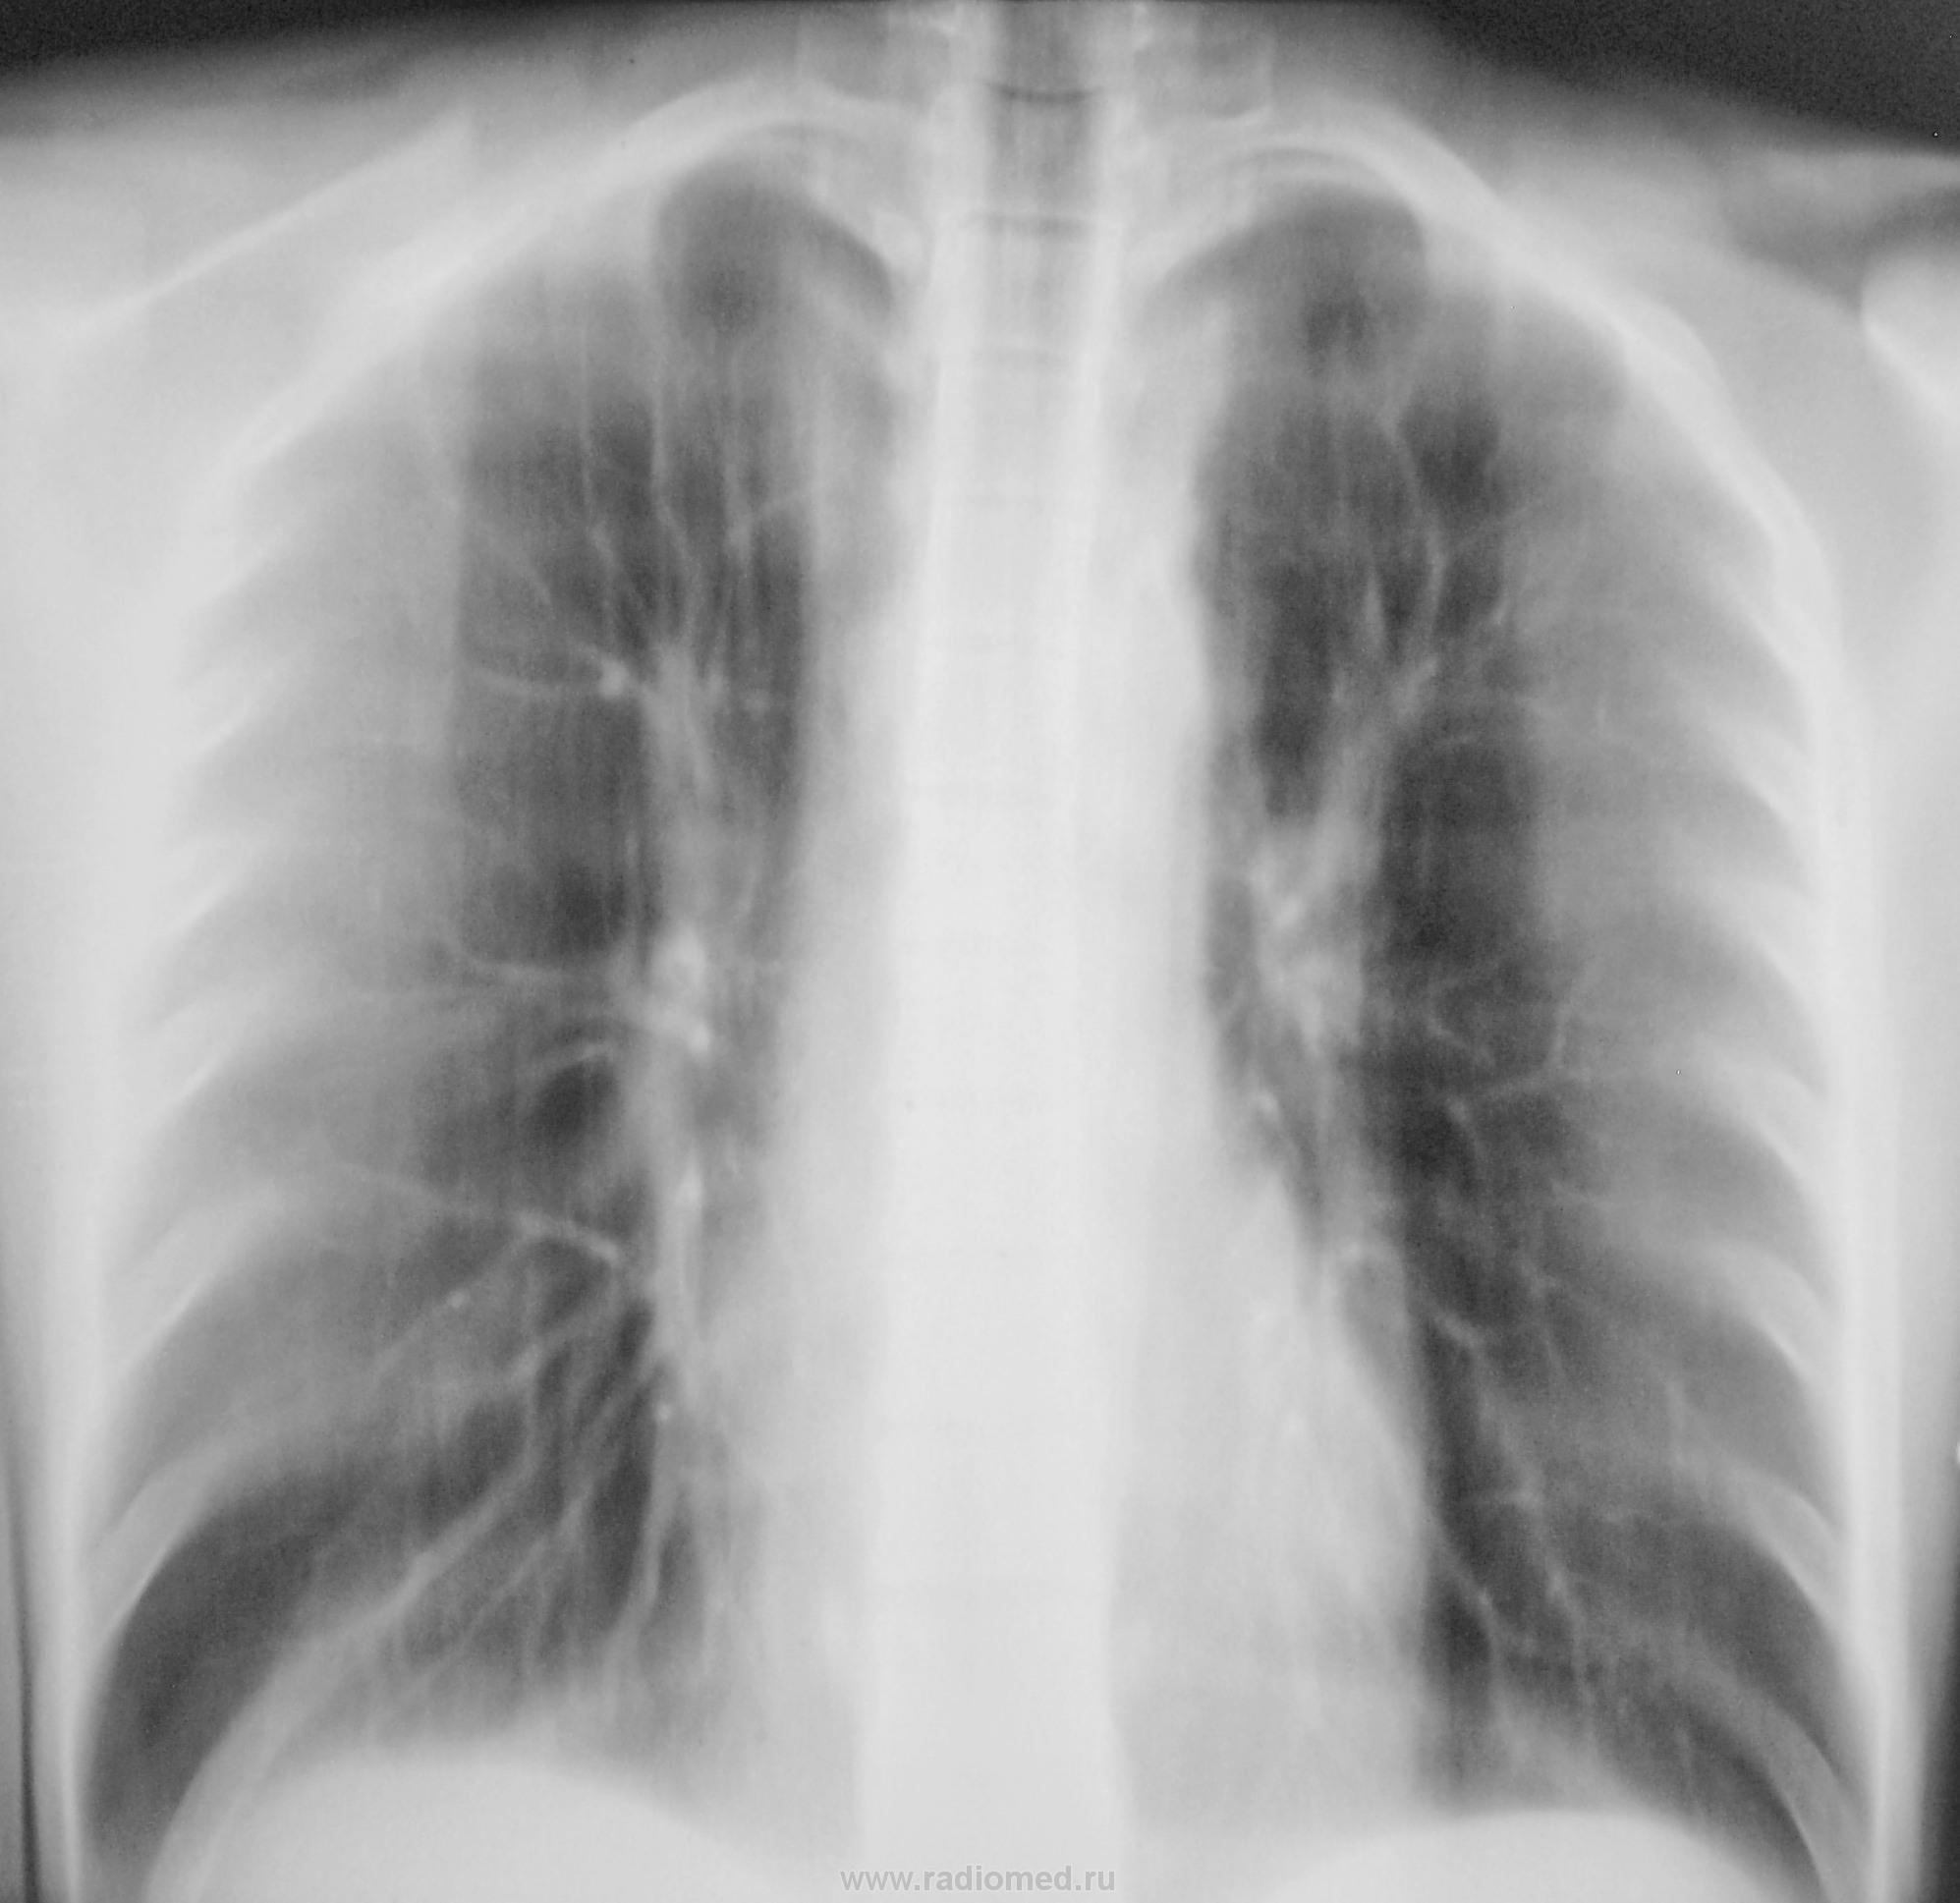

1 срез.

2 срез.

3 срез.

Да, у меня, как правило, "танец" начинается с верхушек.

И, интересует мнение коллег, хотя бы по этому одному срезу.

Смотрите рисунок.  Заключение написано на снимке. Кроме очагов в легких, имеется увеличение паратрахеального лимфатического узла. В ПТД на лечение.  Nikolas